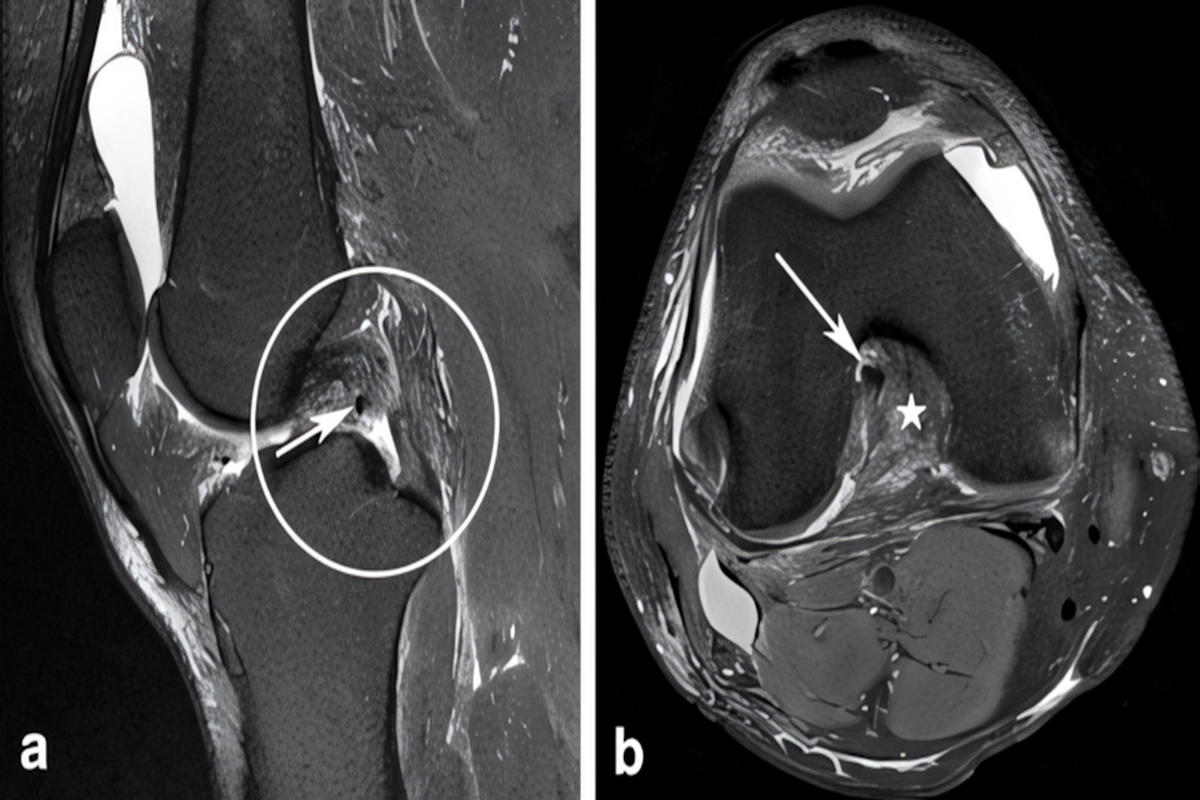

Απεικονιστικά, οι ακτινογραφίες είναι χρήσιμες για αποκλεισμό καταγμάτων. Η μαγνητική τομογραφία (MRI) αποτελεί τη μέθοδο εκλογής, καθώς επιβεβαιώνει τη ρήξη, εκτιμά τη βαρύτητα και ελέγχει για συνοδές κακώσεις. Σε χρόνιες ή σύνθετες περιπτώσεις, η αξονική μπορεί να βοηθήσει σε ειδικές οστικές εκτιμήσεις και σχεδιασμό.